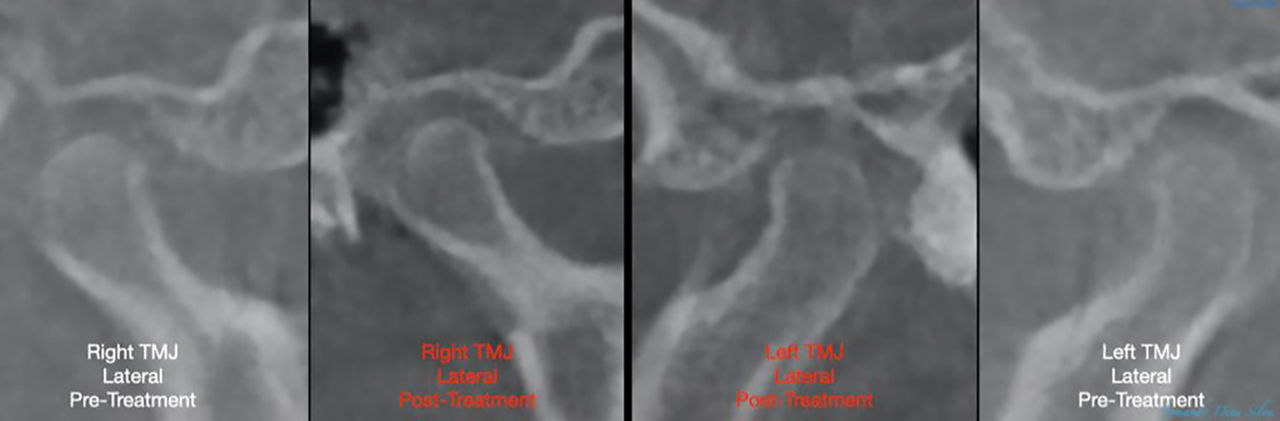

• Molares de clase I logrados con distalización y sin elásticos

• Sin cambios en la posición del cóndilo

Sin cambios en la posición del cóndilo